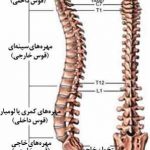

- جراحی ستون فقرات و نخاع (spine surgery)

در مورد جراحی ستون فقرات، درمان شامل اختلالات ساختاری ستون فقرات (اسکولیوزو کیفوز)، تومورهای نخاع، تنگی کانال نخاعی، بیرونزدگی دیسک بین مهرهای و شکستگی مهره و…میباشد و تقریبا عمده مراجعان به جراح مغز و اعصاب را این بیماران تشکیل میدهند.